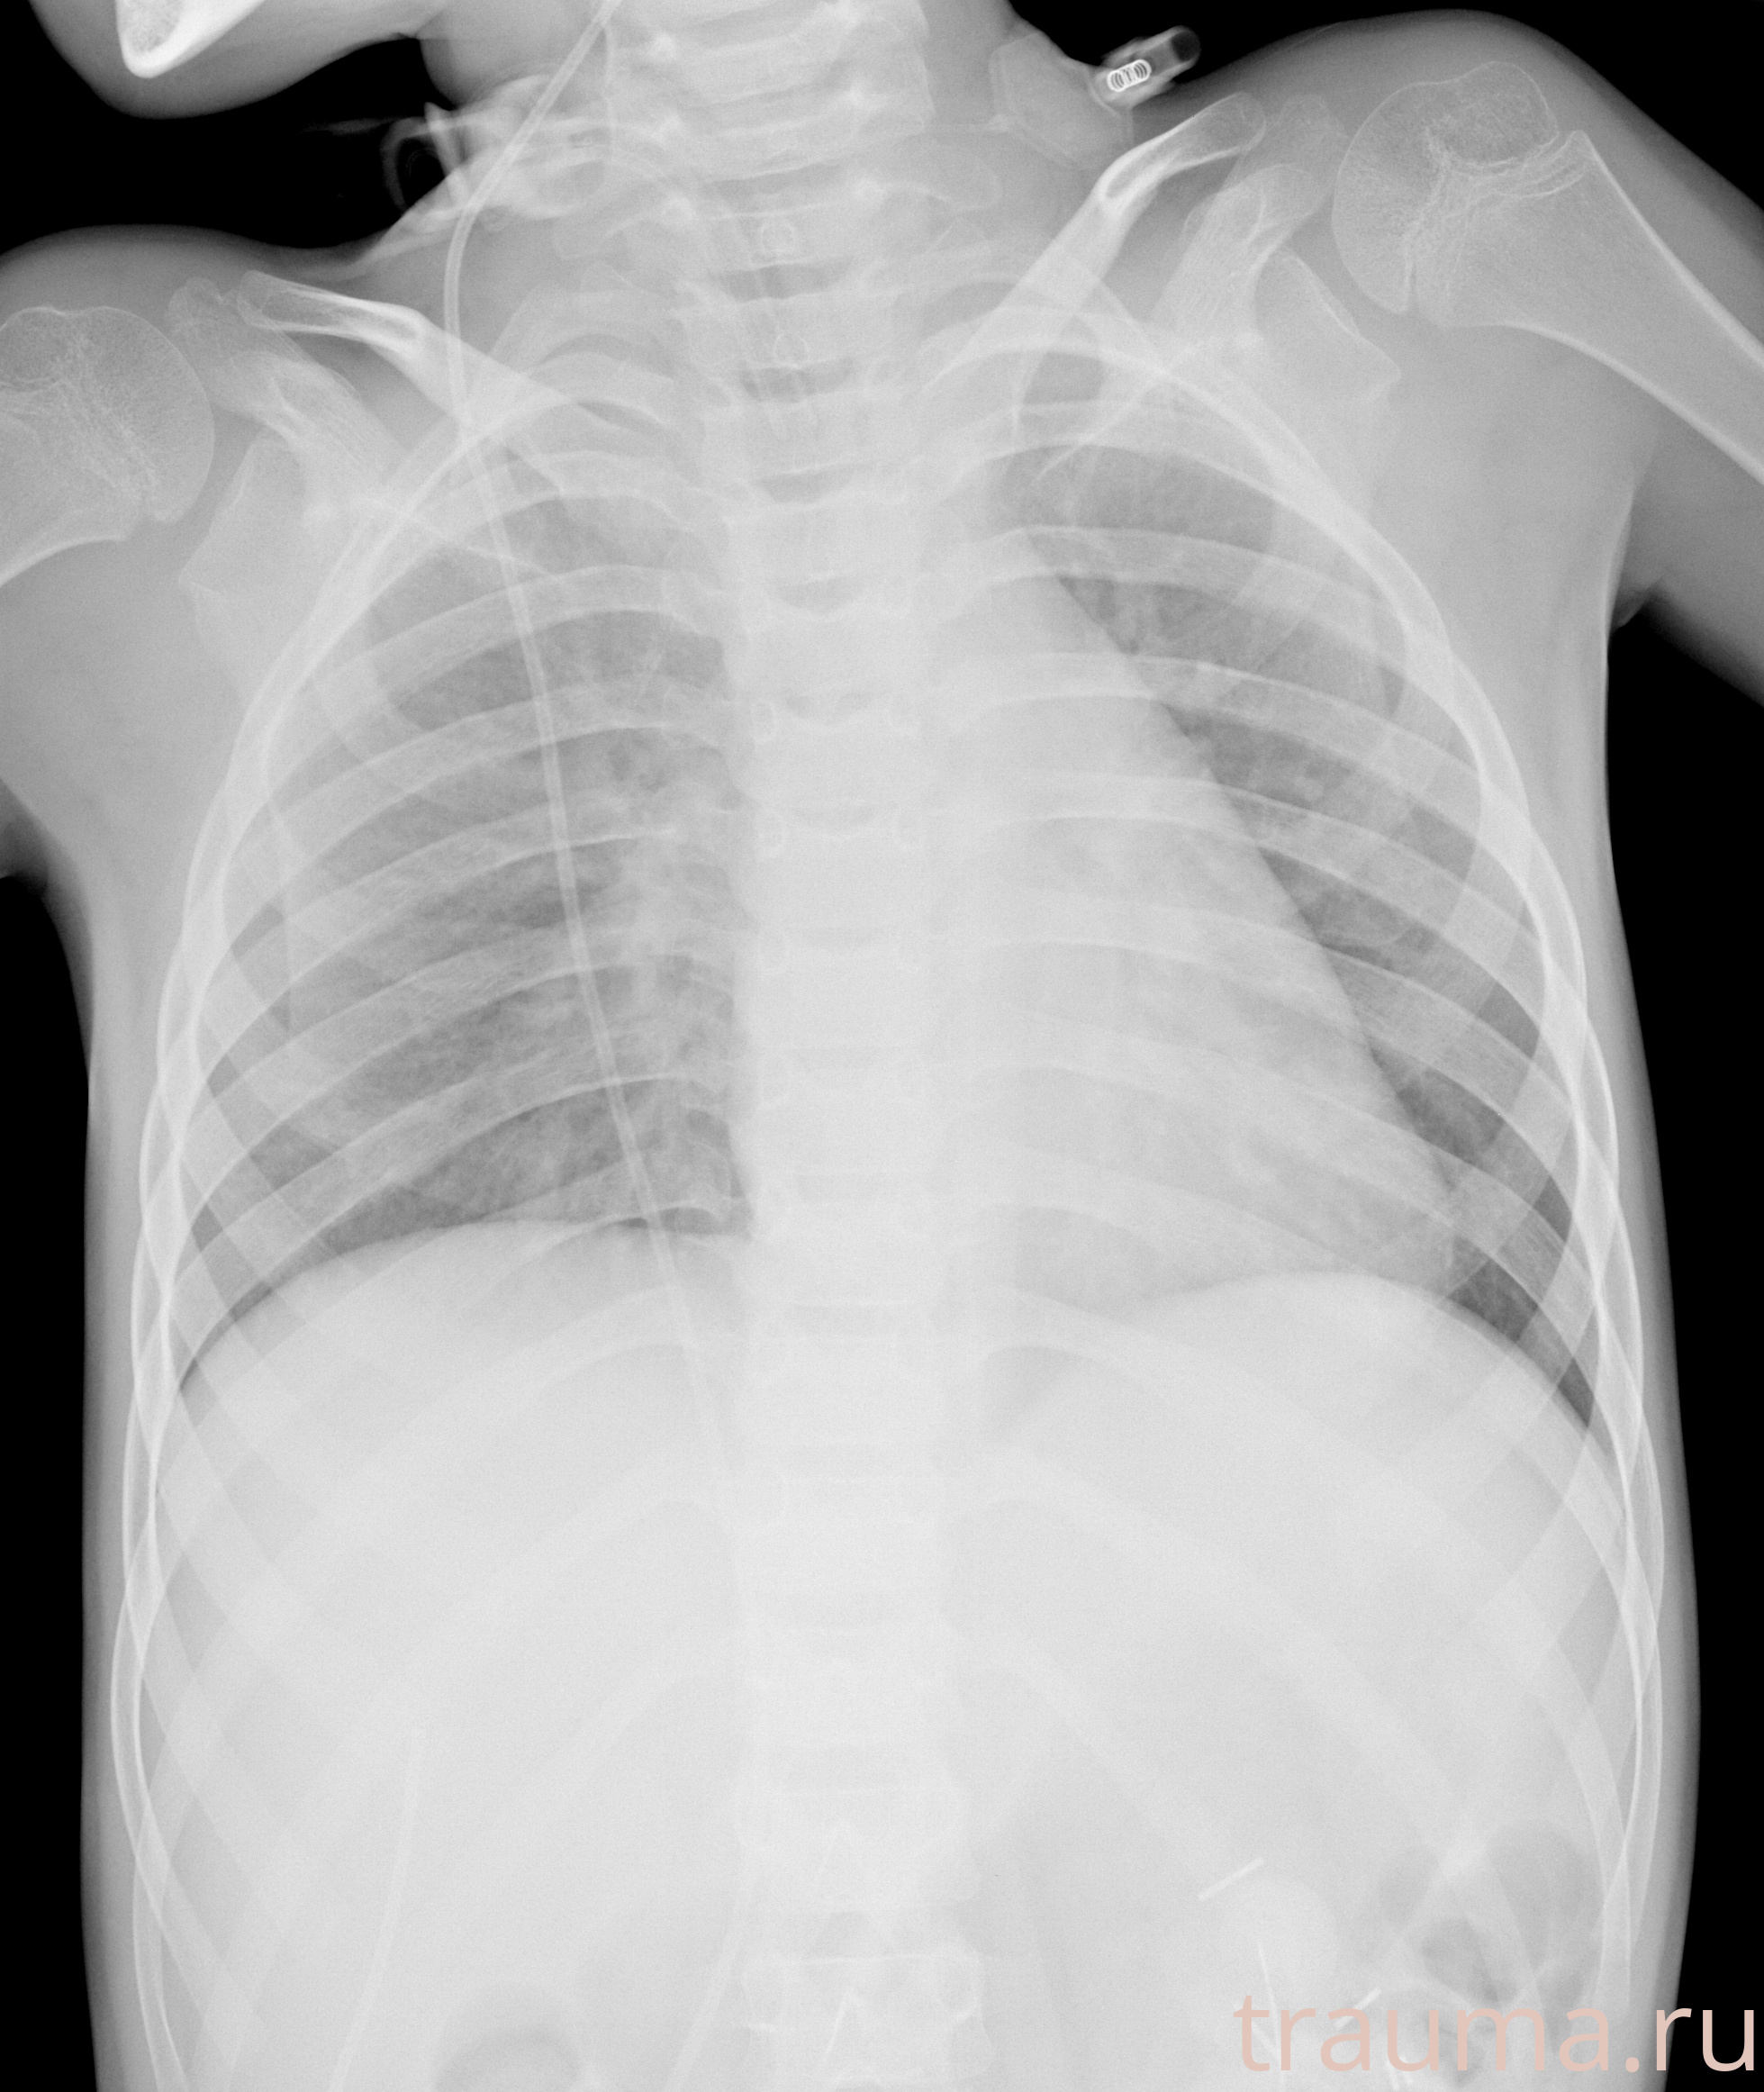

Рентгенограммы

Рентген на дому: по вашему адресу приезжает врач-рентгенолог, травматолог-ортопед с мобильным рентгеновским аппаратом, проводит диагностику травмы или заболевания, делает необходимые рентгенограммы, дает рекомендации по дальнейшему лечению. Получить качественные снимки в домашних условиях возможно благодаря уникальной методике, разработанной МосРентген Центром для института  Склифосовского

Яркость: 1   Контраст: 1   Инвертировать: 0 Увеличение: 1

Перетаскивайте мышь вверх/вниз для контраста, влево/право для яркости. Прокрутка колесом изменяет масштаб. Нажмите Сбросить для возврата к исходному изображению. При увеличении держите мышь в той области, которую хотите рассмотреть.